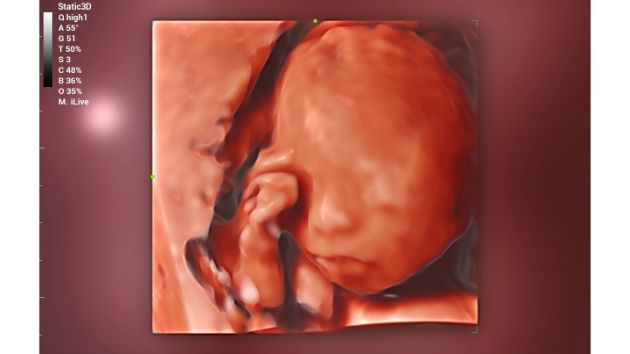

An advanced rendering mode for realistic volume imaging display, brings a better imaging experience by adding lighting rendering effect to the traditional way, allowing human tissue texture to be revealed more clearly.

Consona Series Women Health Solution - iLive feature image

Fetal Embryo 4D

Fetal Face iLive+